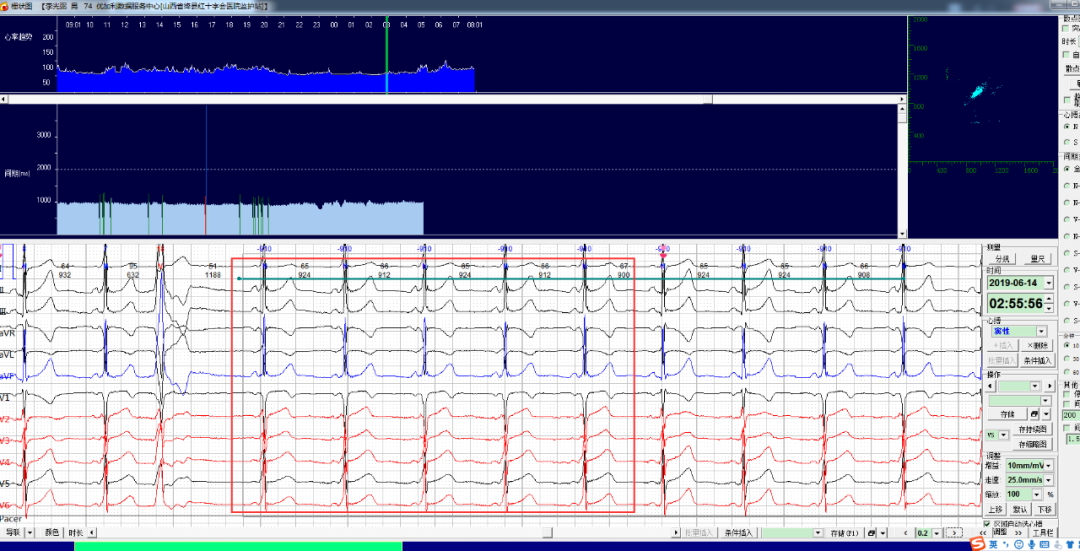

患者駱某,男性,71,病史不詳。

佩戴心安寶動(dòng)態(tài)心電監(jiān)護(hù)儀,監(jiān)測(cè)到如下片段如何分析診斷?